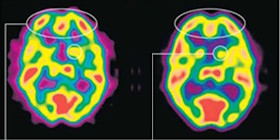

Newberg教授又研究人在說不為人懂的方言時,腦部活動就有很不同的發現,圖二顯示一個人在唱詩歌時(左圖)和說方言時(右圖)腦部掃描,唱詩歌時前腦是活躍的(呈紅色),但說方言時紅色區域減弱很多,表示這人失去了思想,同時他控制情緒和行動的腦部(left caudate)活動也減少,也就是說他進入了失去自控的狀態。另外,他的下丘腦(hypothalamus)部分非常活躍,代表情緒激動,而使身體產生大量血清素(serotonin),也增加了多巴胺(dopamine)的分泌,這些分泌就有如人食了迷幻藥(LSD)一樣,有著興奮刺激的感覺(get high),這種異常興奮感覺有兩種後果,一是給人一種快樂的感覺,二是可使人上癮,回去再重複同一活動,追求上次的興奮體驗。

圖二:比較唱詩歌(左邊)和說方言時(右邊)的腦掃描,前腦活動減少,控制情緒和行動的腦部活動也減少。